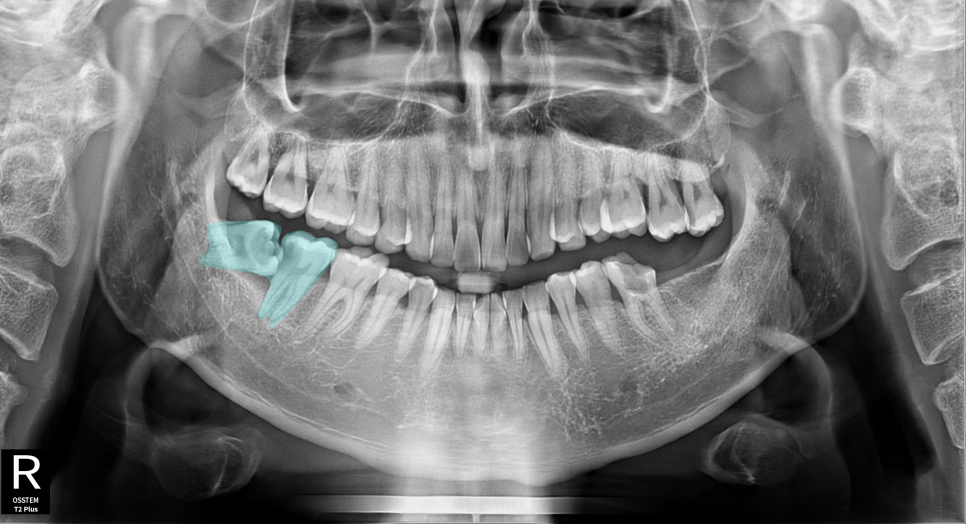

촬영일:2025.07.15 (첫 내원)

[발치 진단을 받은 이유]

40대 남성 환자분은 다른 치과에서 오른쪽 아래 어금니 발치를

권유받고 불안한 마음으로 내원하셨습니다.

X-ray 검사 결과:

- 사랑니(#48)가 옆으로 완전히 누워 자람

- 바로 앞 어금니(#47)를 지속적으로 압박

- 신경과 가까운 위치라 발치 시 신경 손상 위험 존재

- 그 결과 #47 어금니가 충치와 잇몸 손상으로 크게 망가진 상태

모든 치아에는 각각의 고유 번호가 있습니다.(이미지 참고)

치과에서는 이 치아 번호를 통해 정확히 어떤

치아를 말하는지 빠르게 구분할 수 있습니다.

이번 환자분이 발치 진단을 받았던

가장 큰 원인도 바로 이 48번

즉, 사랑니의 위치 때문이였습니다.